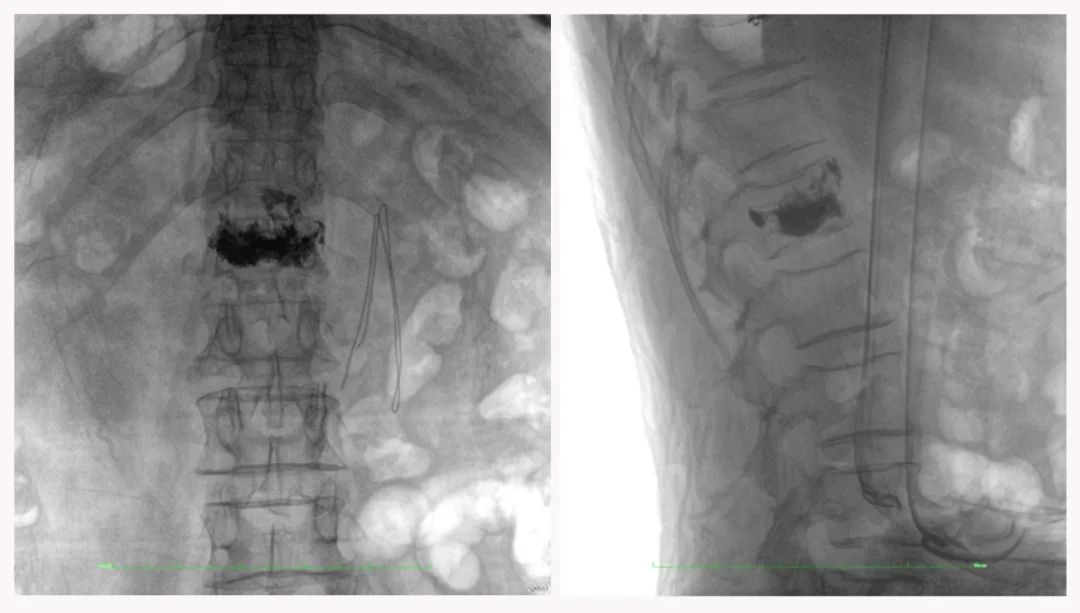

病例2 踝關(guān)節(jié)骨折復(fù)位(31歲)

在踝關(guān)節(jié)骨折復(fù)位手術(shù)中,用三維C可以更好地觀察骨折部位的復(fù)位情況:

正側(cè)位影像觀察脛腓聯(lián)合復(fù)位良好

從三維影像看,復(fù)位欠佳,貼合度不夠